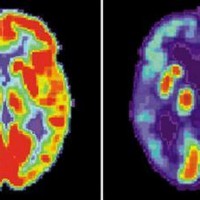

قام أطباء الأعصاب في الصين بتشخيص إصابة شاب يبلغ من العمر 19 عاماً بمرض «ألزهايمر»، ما يجعله أصغر شخص يتم تشخيصه بهذا المرض في العالم، وفقاً لموقع «ساينس أليرت».

وبحسب الموقع، بدأ الشاب يعاني من تدهور الذاكرة في سن 17 عاماً، وتفاقمت الخسارة المعرفية مع مرور السنين.

وغالباً ما يُعتقد أن «ألزهايمر» مرض يصيب كبار السن، ومع ذلك فإن الحالات المبكرة، التي تشمل المرضى الذين تقل أعمارهم عن 65 عاماً، تمثل ما يصل إلى 10 في المائة من جميع التشخيصات.

ويمكن لجميع المرضى الذين تقل أعمارهم عن 30 عاماً تقريباً تفسير مرض «ألزهايمر» من خلال طفرات جينية مرضية، ما يضعهم في فئة مرض «ألزهايمر» العائلي، وكلما كان الشخص أصغر سناً عندما يتم تشخيصه، زادت احتمالية أن يكون نتيجة الجين الذي ورثه.

ومع ذلك، لم يتمكن الباحثون في جامعة العاصمة الطبية في بكين من العثور على أي من الطفرات المعتادة المسؤولة عن البداية المبكرة لفقدان الذاكرة لدى الشاب الذي تم تشخيصه، ولا أي جينات مشتبه بها عندما أجروا بحثاً على مستوى الجينوم.

وقبل عامين من إحالته إلى عيادة الذاكرة، بدأ المريض المراهق يكافح من أجل التركيز في الصف. أصبحت القراءة صعبة أيضاً وتراجعت ذاكرته قصيرة المدى. في كثير من الأحيان، لم يكن يتذكر أحداث اليوم السابق، وكان دائماً يضع أغراضه في مكانها.

في النهاية، أصبح التدهور المعرفي سيئاً للغاية، ولم يتمكن الشاب من إنهاء المدرسة الثانوية، رغم أنه لا يزال بإمكانه العيش بشكل مستقل.

بعد عام من إحالته إلى عيادة الذاكرة، أظهر تراجعاً في الاستدعاء الفوري، وكانت درجة الذاكرة الكاملة للمريض أقل بنسبة 82 في المائة من نظرائه في سنه، في حين أن درجة ذاكرته الفورية كانت أقل بنسبة 87 في المائة.